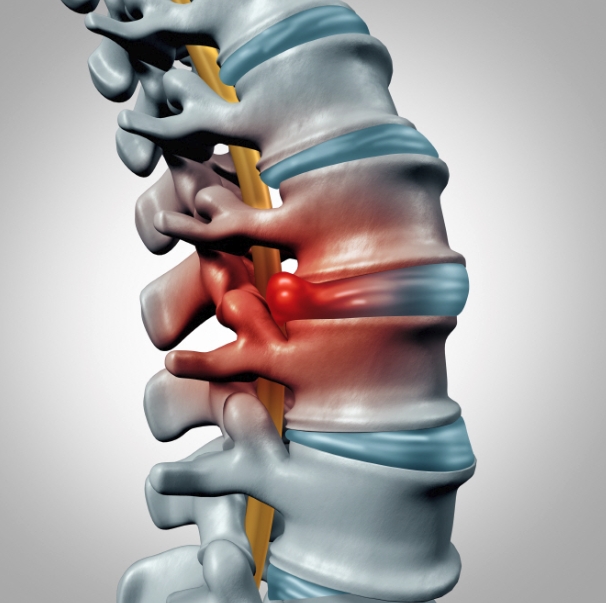

일자목은 본래 C자 형태로 휘어 있어야 하는 경추(목뼈)의 곡선이 무너지면서 일직선처럼 펴진 상태를 말합니다. 겉으로 보기에는 큰 차이가 없어 보여도, 머리의 무게가 그대로 목과 어깨에 실리면서 다양한 증상으로 이어집니다. 주변 사람들 이야기를 들어보면 목이 뻣뻣하게 굳은 듯한 느낌이 계속되고, 고개를 숙이거나 젖힐 때 어딘가에서 뻐근하거나 저릿한 느낌이 든다고 말하곤 합니다. 하루 종일 컴퓨터 앞에 앉아 있는 직장인이나 스마트폰을 자주 보는 사람들에게 흔하게 나타나는 증상이기도 하지요.

일자목과 거북목은 비슷한 듯하지만 그 원인과 진행 양상에서 차이가 있습니다. 일자목은 경추의 C자 곡선이 사라지며 직선으로 변한 상태이고, 거북목은 그보다 더 심화되어 목이 몸통보다 앞으로 빠져나온 체형까지 바뀐 경우입니다. 쉽게 말해, 일자목은 정적인 구조의 변화라면 거북목은 역동적인 자세의 변형이라고 할 수 있죠. 일자목은 비교적 초기에 발견되면 교정이 어렵지 않지만, 거북목은 어깨 말림이나 등 근육의 긴장, 허리 통증까지 이어지기 때문에 더 복잡한 교정 과정이 필요합니다.